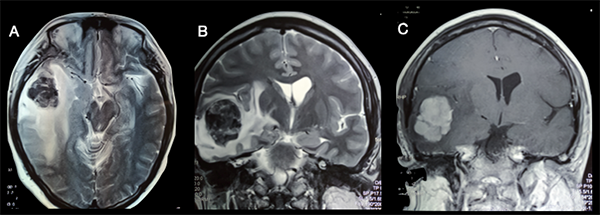

La resonancia magnética nuclear (RMN) evidenciaba una imagen isointensa en T1, hipointensa en T2 con zonas heterogéneas, con realce homogéneo tras la administración de contraste endovenoso, de 3,5 X 3,0 X 5 cm de diámetros máximo, localizada en región temporal derecha asociada a edema perilesional que desplaza estructuras vecinas, comprimiendo parcialmente cavidades ventriculares derechas (Figura 1).

Figura 1

: A) RMN T2 corte axial evidencia lesión hipointensa con sectores heterogéneos, bien delimitada ubicada en el lóbulo temporal derecho con edema perilesional que desplaza estructuras adyacentes. B) RMN T2 corte coronal. C) RMN T1 con contraste evidencia lesión que capta contraste en forma homogénea.